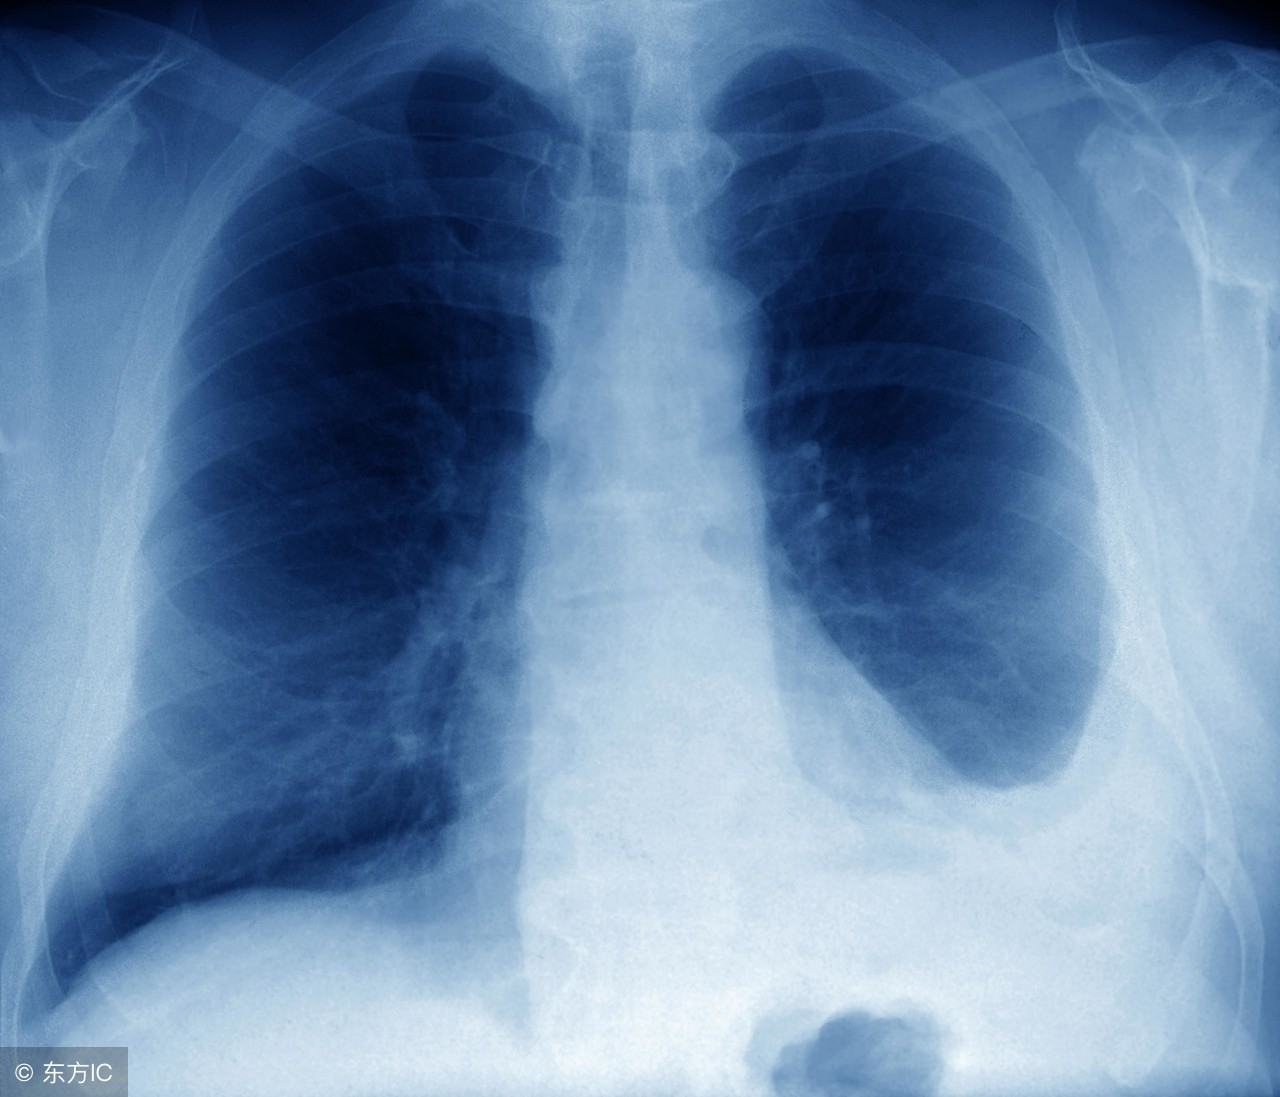

其它转移形式可能导致疼痛的方式都不一样。如果腹腔内广泛转移,多是腹部胀痛为主,肿瘤压迫肠管导致肠梗阻,会引起阵发性痉挛性疼痛;如果出现脑转移,会引起头晕、头胀痛,持续性,放疗可适当缓解;出现肺转移,轻度可没有症状,严重时会出现胸闷、胸痛等症状,化疗为主,胸水多时,适当放胸水,缓解症状。

左侧胸腔积液